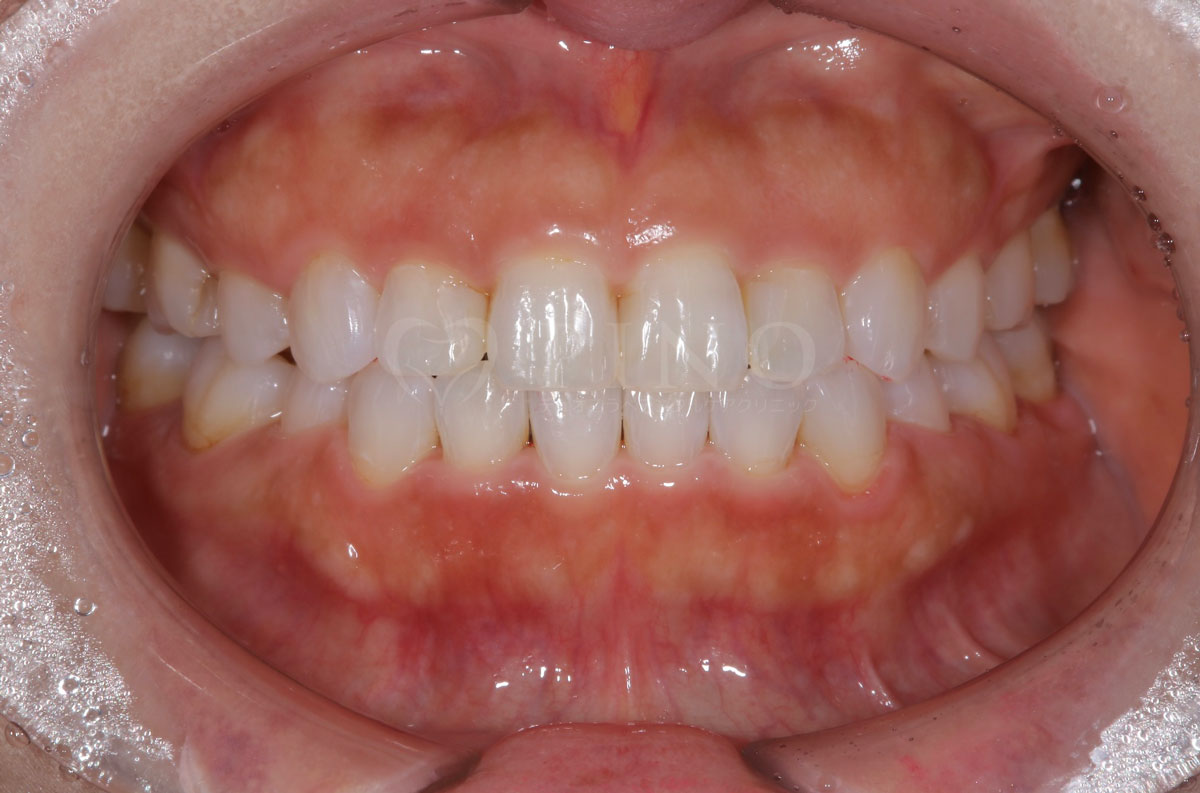

症例8:歯が全体的にガタガタして気になる(30代女性)

主訴 歯が全体的にガタガタして気になる 診断名 上下顎1級叢生 治療方法 マウスピース全顎矯正 抜歯 あり 上2本 オルソパルス あり 治療期間 1年5ヶ月 費用 891,000円+補綴治療費(セラミック320,000円) 副作用・注意点 歯を抜く際に痛みを伴う可能性がある、矯正後後戻りを防ぐためリテーナーの使用が必要となる -